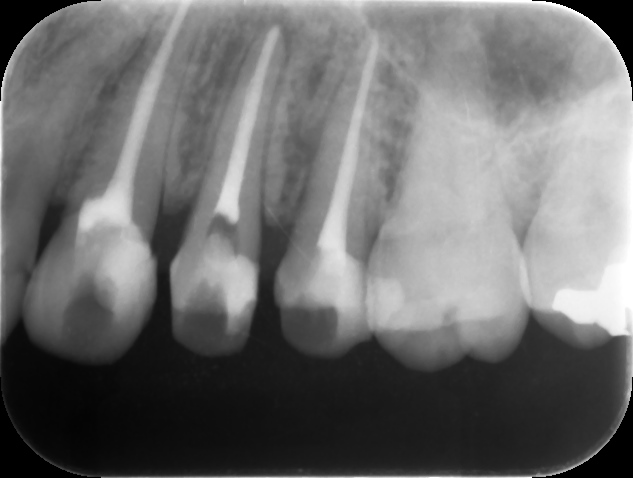

治療後レントゲン。適切な補綴(被せ物)により治療を終了。的確な診断および治療を行うことで、長年の悩みから解放された。我々は、無暗に患者さんの大切な人生の時間を奪ってはいけない。